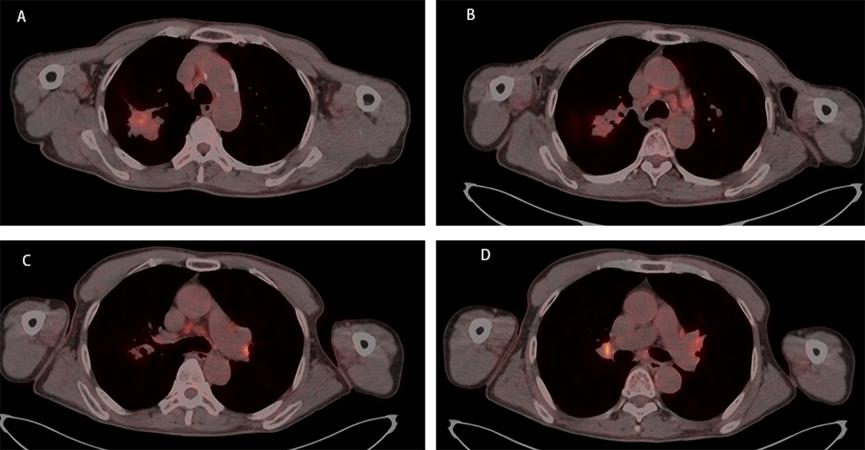

A 67-year-old male, with a continuous smoking history of over 30 years, was admitted to hospital for blood in phlegm half a month and was diagnosed as right lung upper lobe adenocarcinoma with right hilar and mediastinal lymph node metastasis examined by PET-CT. CT-guide needle biopsy was performed, and subsequent HE staining and immunohistochemistry confirmed adenocarcinoma with PD-L1(+,5%). Quantitative polymerase chain reaction (qPCR) assay of 10 genes in primary tumor tissue showed G12S\G12D mutation in exon 2 of KRAS gene. Neoadjuvant chemotherapy is administered to patients anticipated to benefit from subsequent adjuvant chemotherapy; however, it only modestly enhances 5-year recurrence-free and OS rates by about 5% to 6% [7]. The incorporation of immune checkpoint inhibitors (ICIs) into neoadjuvant chemotherapy demonstrates potential, having a minimal impact on the likelihood of significant perioperative complications or mortality, while presenting new opportunities for managing treatable NSCLC, with a major pathological response rate varying between 21% and 45%. Additionally, induction with ICIs does not increase toxicities that could delay surgical interventions [8]. Following the results of the CheckMate-816 study, immunochemotherapy is now suggested as a neoadjuvant approach [9]. After discussing in the multidisciplinary team (MDT), in view of the difficulty of operation, three cycles of neoadjuvant Camrelizumab(anti-PD-1 antibody) combined with pemetrexed and carboplatin were administered to the patient. However, repeat imaging after two cycles demonstrated concern for disease progression with right mediastinal lymph node increased and new left hilar and mediastinal(4L) lymph node metastasis. But the right upper lung lesions became significantly smaller with the tumor biomarker, CEA, NSE and Cyfra21-1 continued to decline (Figure 1). However, the side effects of immunochemothrapy are small, with no high-grade toxicities, the patient chose to continue to receive one more cycle treatment. Repeat imaging after one more cycle treatment demonstrated that decreasing of the primary lesion but stable right mediastinal and left hilar and mediastinal lymph node (Figure 2a-d). Positron emission tomography-computed tomography (PET-CT) was performed and showed that the local residual tumor with slightly high FDG metabolism, hilar and mediastinal lymph node enlargement with high FDG metabolism (Figure 3A-D). After the re-MDT, it was considered that the tumor shrank significantly and the tumor markers continued to decrease. The nature of the contralateral hilar lymph nodes was the same as that of the 4L group lymph nodes. It is recommended to complete the EBUS-tbna examination and puncture the 4L group lymph nodes. Lymph node biopsy of group 4L lymph node by Ebus-tbna showed no cancer tissue was found. In view of the possibility of pseudoprogression, after a sufficient communication, the patient underwent a right lung upper lobectomy and hilar and mediastinum lymph node dissection. Surgical pathology showed there was no residual cancer tissue, which achieved pathological complete remission, and the enlarged lymph nodes including 4L were presented as change after immunotherapy, no visible tumor cells existed. Now, the patient had finished all treatment and reexamination periodically for 13 months, no evidence of relapse or metastasis exist.